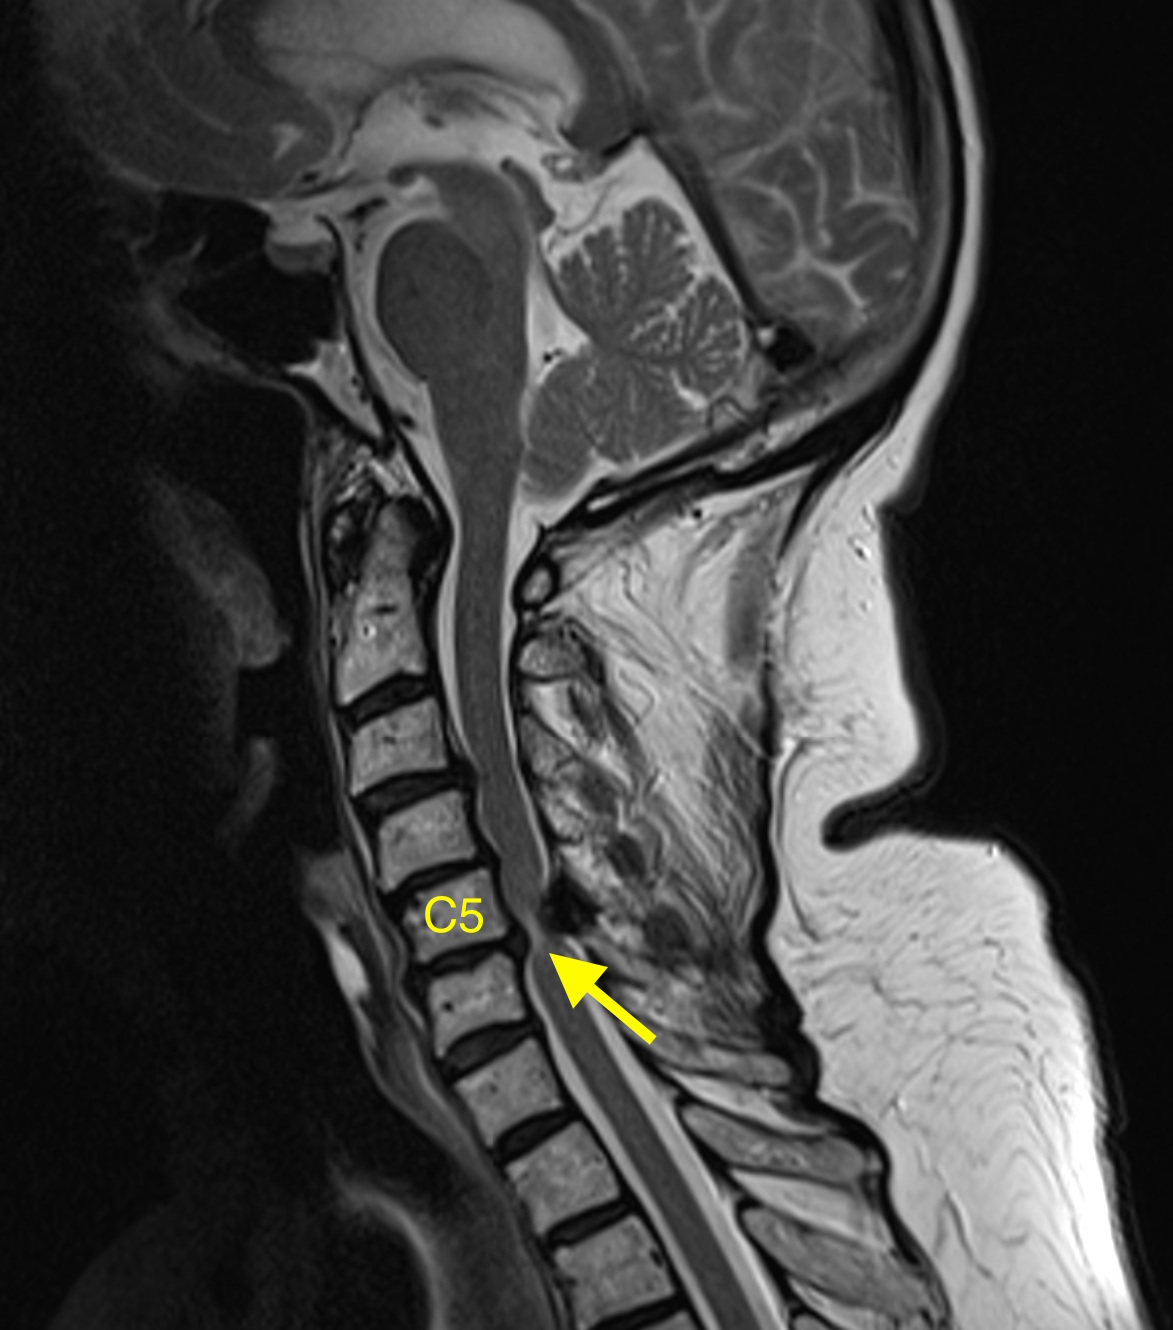

Cervical myelopathy – MRI – Radiology at St. Vincent’s University Hospital

Bone Spur In Neck C5 C6 – NeckProAdvice.com

Sagittal T1-weighted MRI of his cervical spine. | Download Scientific …

Cervical bone spur presenting with spontaneous intracranial hypotension …